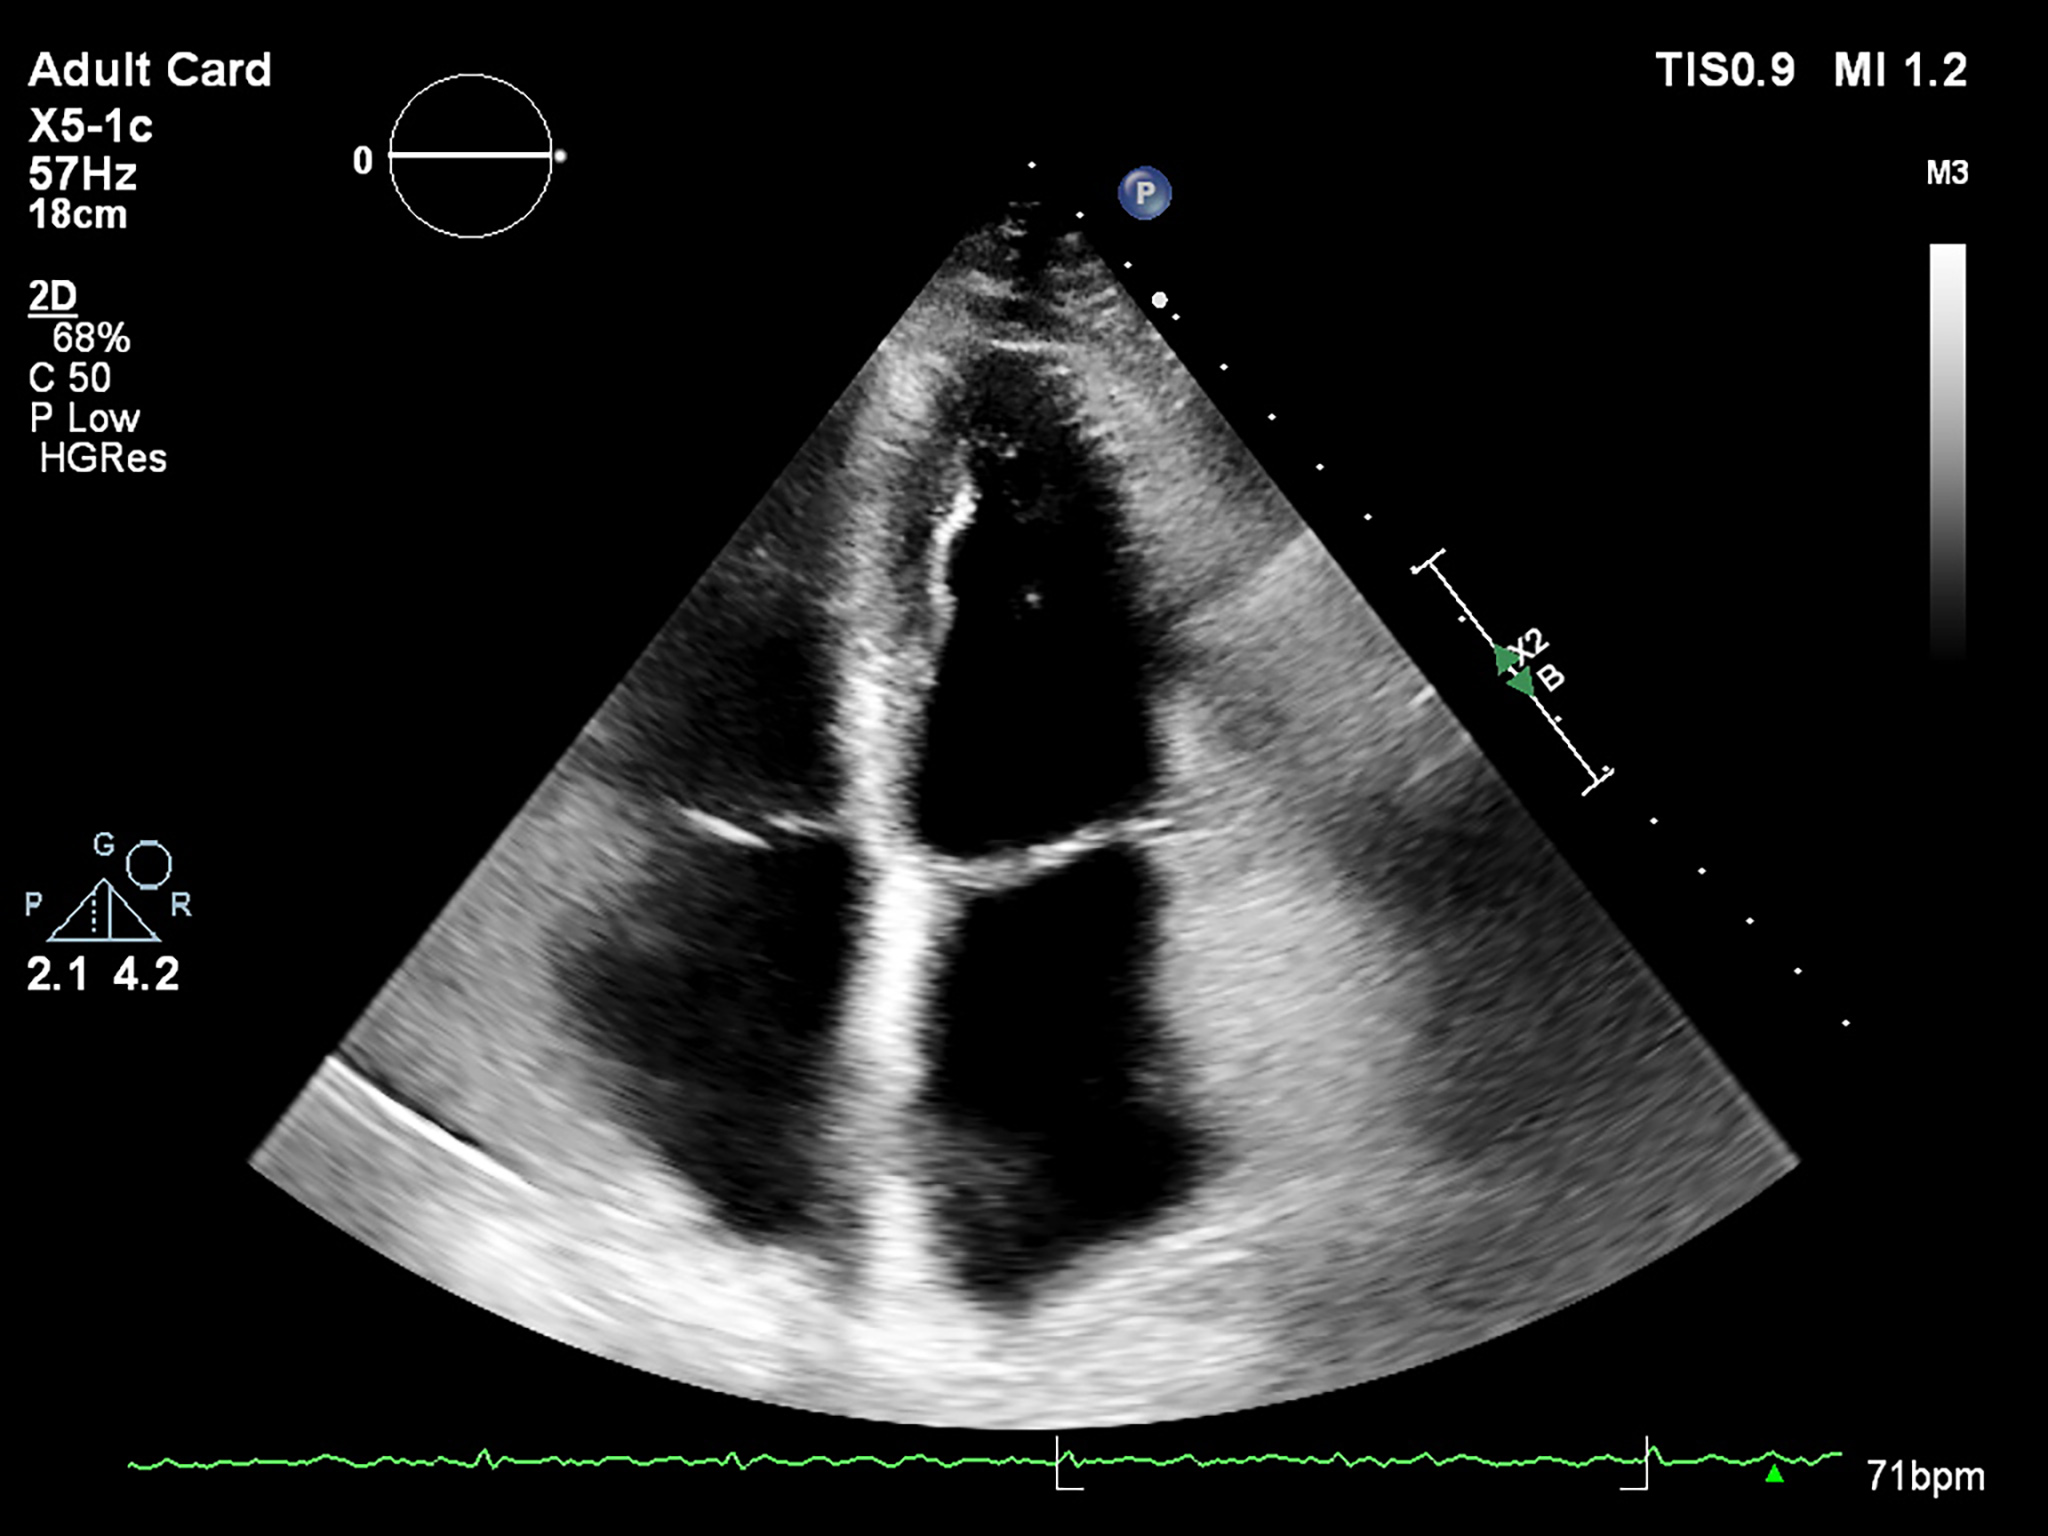

Fig. 2.

Fig. 2.Bidimensional echocardiography – 4 chambers view, maximum left atrium dedicated view.

An enlarged LA indexed volume is defined as more than 34 mL/m

LA enlargement usually occurs as a result of persistent chronic pressure

overload. The LA volume evaluation represents an integral part of evaluating

ventricular diastolic function. Bi-dimensional imaging obtained by 2D-E does not

reflect the true LA size, and three-dimensional echocardiography (3D-E) should be

superior for accurate measurement. Atrial volumes by 3D-E (Fig. 3) correlate with

2D-E assessment, but values are higher, as 2D-E underestimates LA volumes in

comparison with other imagistic techniques (especially cardiac magnetic

resonance, which is the gold standard). Most studies evaluated LA volumetry using

dedicated left ventricular programs. Though data is still lacking for normal

ranges, a study in healthy volunteers by Badano et al. [38] determined a

maximum LA index volume in 3D-E of 43 mL/m

Fig. 3.

Fig. 3.Left atrium tridimensional volume and function using 3D-E speckle tracking with a dedicated software.